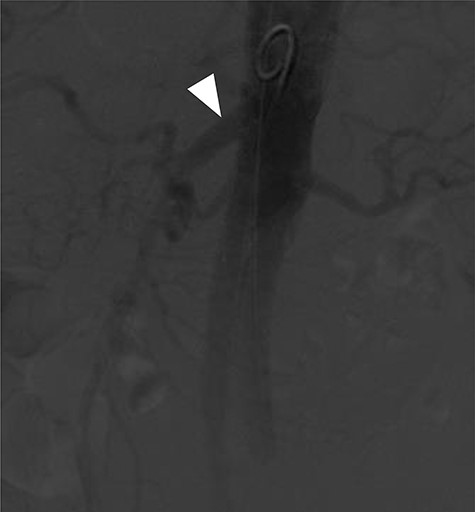

Terumo Aortic Anaconda three-vessel fenestrated and bilateral iliac branched graft was used for repair and was deployed in perirenal position with stents to the SMA and both renal arteries. Surgical arterial access was via left axillary artery (LAA) and percutaneous access was ultrasound-guided via common femoral arteries (CFA) bilaterally. Cannulation of left renal artery (V12 5 × 22 mm) and SMA (V12 9 × 32 mm) was via CFA and right renal artery (V12 5 × 22 mm) was through LAA. There was intra-operative difficulty in SMA cannulation, which was eventually cannulated after repositioning of graft (Fig. 3). Final intra-operative angiogram showed patent renal arteries bilaterally, SMA and common iliac arteries bilaterally (Fig. 4). Post-operatively, he was transferred to surgical high dependency unit (HDU). Three days post FEVAR, he developed abdominal pain, haematemesis and melaena with significantly raised inflammatory markers. CT mesenteric angiogram showed an ischaemic small bowel segment. A necrotic gallbladder was found incidentally during laparotomy, which required cholecystectomy after 20 cm segment of small bowel had been resected and decision was made to not anastomose the small bowel due to the intra-operative findings. A relook laparotomy was performed for small bowel anastomosis and drainage of bile collection found in the gallbladder fossa. Histology results later confirmed infarcted gallbladder with extensive acute inflammation as well as congested, ischaemic and focally infarcted small bowel segment with peritonitis.

Completion angiogram showing good filling of proximal SMA (arrowhead), renal arteries and common iliac arteries.